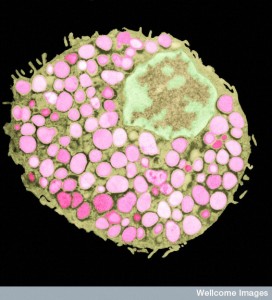

Granulocytes are a category of white blood cells that have different compartments of molecules that are seen by microscope. The most prominent is the leukocyte, but others include eosinphils, basophils and mast cells (with histamine granules).